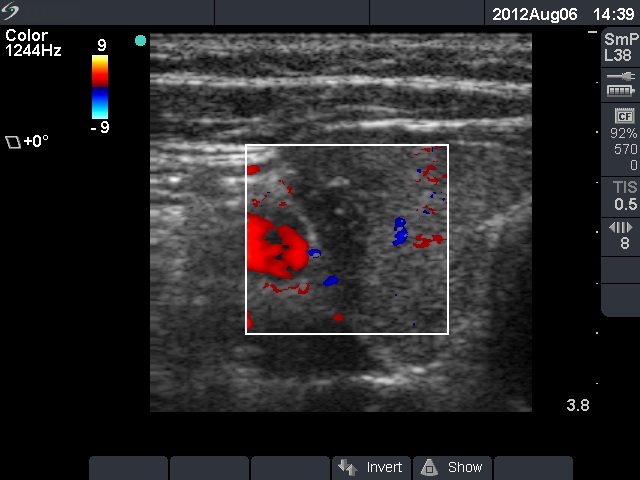

Ultrasonography: The thyroid was echonormal. There was a hypoechogenic lesion with blurred borders and microcalcifications in the right and a moderately hypoechogenic nodule in the left lobe. The former was not present on the previous examination.